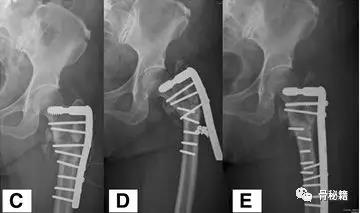

来一个比较有意思的病例大家讨论:

一个双膦酸盐治疗5年的患者粗隆下非典型骨折

采用了髓内钉固定,术后一年内固定失效

更换了DCS+植骨固定,术后四个月又发现了内固定失效再次更换了更长的DCS

这次的固定能成功吗?